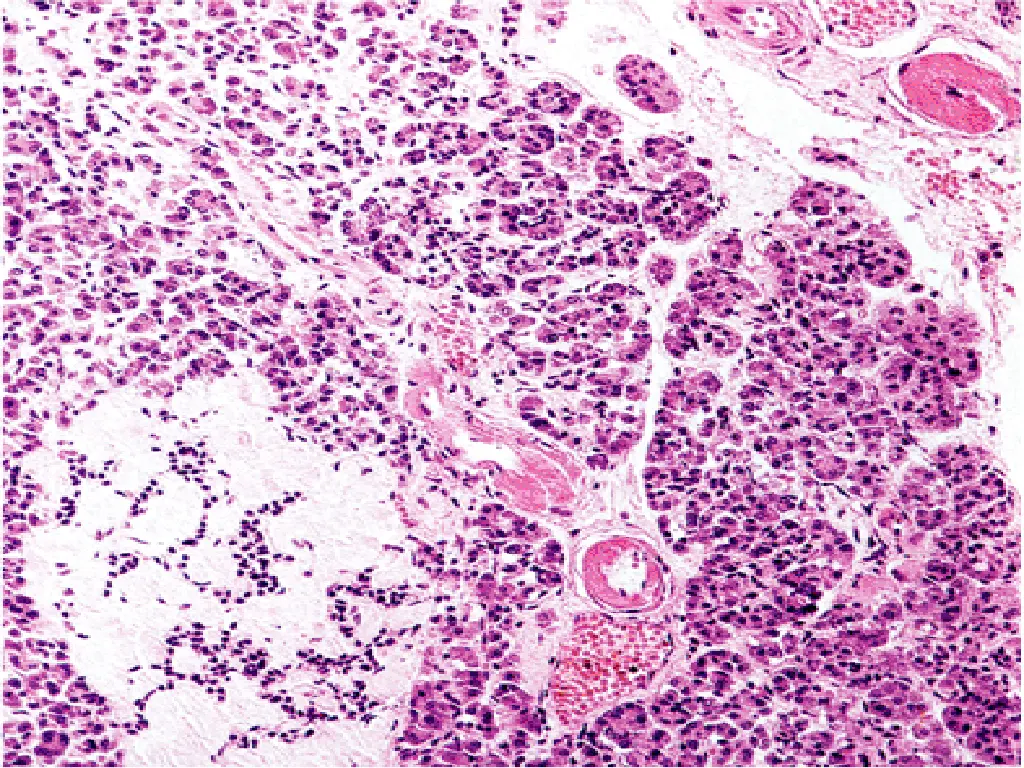

2- AUTOIMMUNITY: Patients who die shortly after the onset of the disease often exhibit an infiltrate of mononuclear cells in and around the islets of Langerhans, termed insulitis

Cell-mediated immune mechanisms are fundamental to the pathogenesis of T1DM ,CD8+T lymphocytes pre- dominate, although some CD4+cells are also present. The infiltrating inflammatory cells also elaborate cytokines, for example, IL-1, IL-6, interferon-alpha, and nitric oxide, which may further contribute to B cell injury. An autoimmune origin for T1DM was initially suggested by the demonstration of circulating antibodies against components of the B cells (including insulin itself) in most newly diagnosed children with diabetes.

Lymphocytic infiltrate in the islets (insulitis), sometimes accompanied by a few macrophages and neutrophils As the disease becomes chronic, the B cells of the islets are progressively depleted of Beta cells Fibrosis of the islets is uncommon. In contrast to T2DM, deposition of amyloid in the islets of Langerhans is absent in T1DM. The exocrine pancreas in chronic T1DM often exhibits diffuse interlobular and interacinar fibrosis, accompanied by atrophy of the acinar cells.